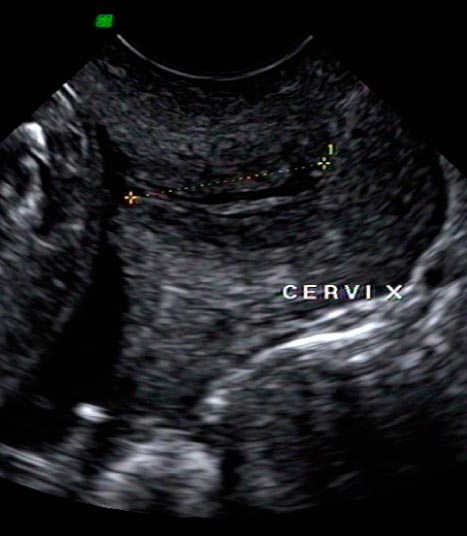

Somos expertos en detección temprana de anomalías. Brindamos una gama completa de Ultrasonidos Fetales y Ecografías 5D-7D: